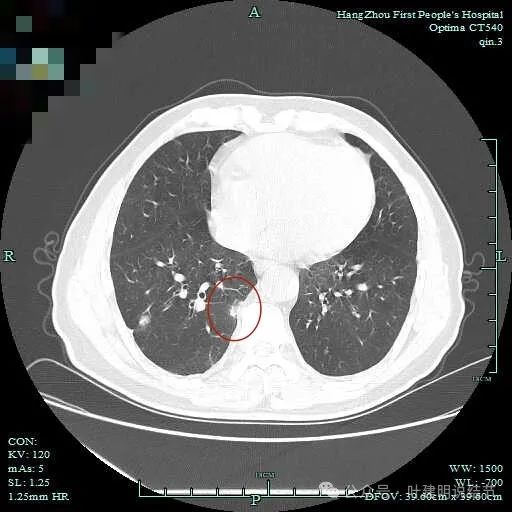

上图呈结节状,表面不平,有少许磨玻璃成分。

结节状,密度高,边缘欠光滑。

与脊柱之间有间隙,表面有细毛刺。

表面不平,似有细支气管截断征。

边缘不平毛糙。

像慢性炎似的。

瘤肺边界欠清。

边缘区淡磨玻璃密度。